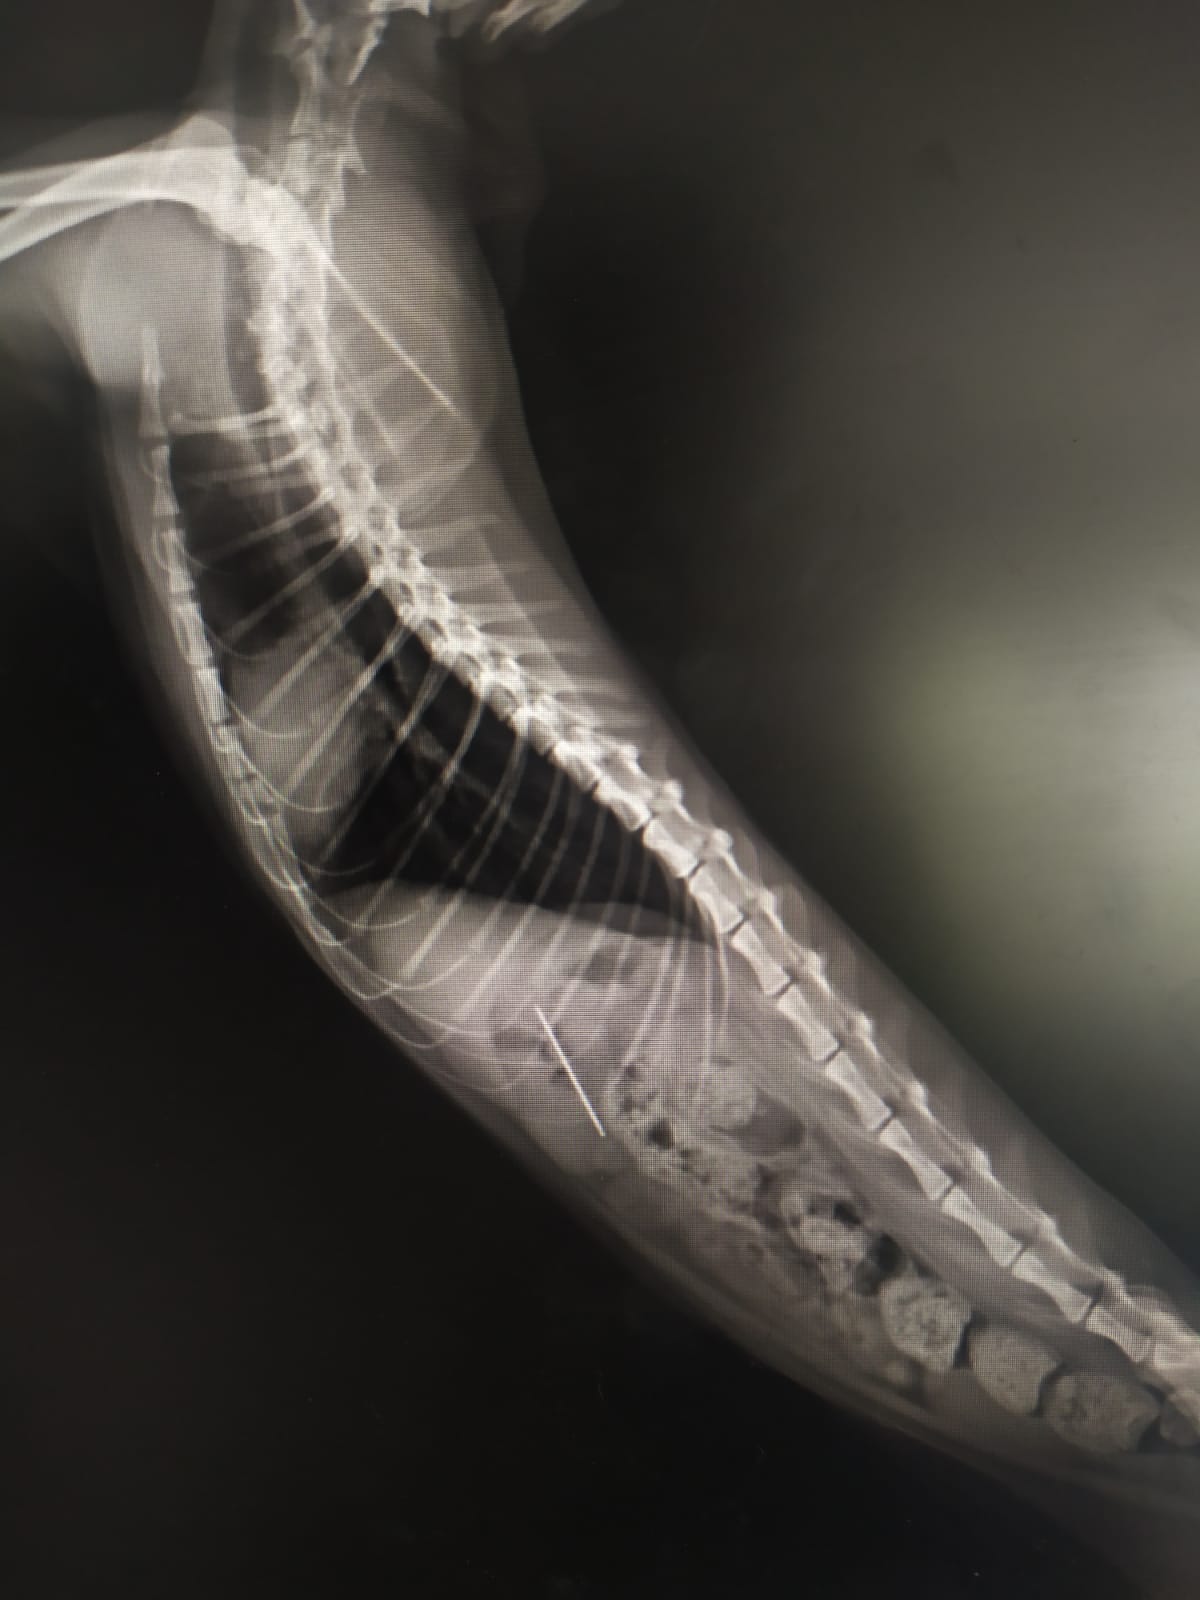

Kentte bulunan özel bir veteriner kliniğinde muayene edilen kedinin röntgeni çekildi.

Kedinin midesinde tespit edilen dikiş iğnesi endoskopiyle çıkarıldı.